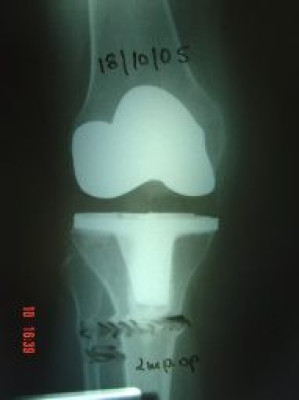

Artrosis de rodilla derecha por valgo severo

Envíado por Dr. Ricardo Antonio Gómez G.